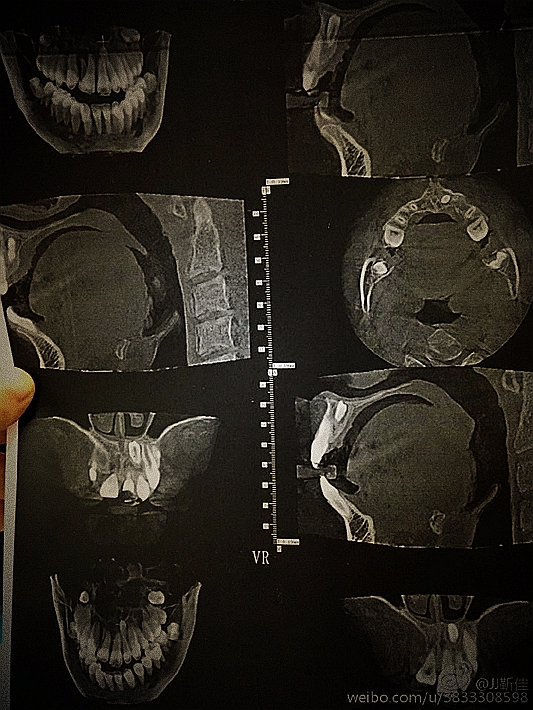

ct定位

額外牙拔除

好大的額外牙

術(shù)后拍片